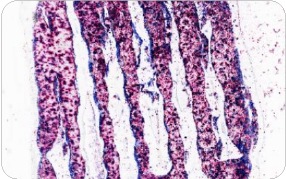

3D打印骨材料切磨片 Masson染色

小鼠顱骨切磨片 VG染色 80x

比格犬下頜骨切磨片 HE染色

比格犬下頜切磨片 甲苯胺藍染色

骨切磨片 HE染色

犬下頜骨切磨片 Masson染色